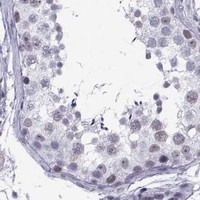

Enhanced - Independent antibodies

Protein distribution across 45 tissues similar between the independent antibodies HPA076123 and HPA077266.

Cerebral cortex

Colon

Kidney

Testis